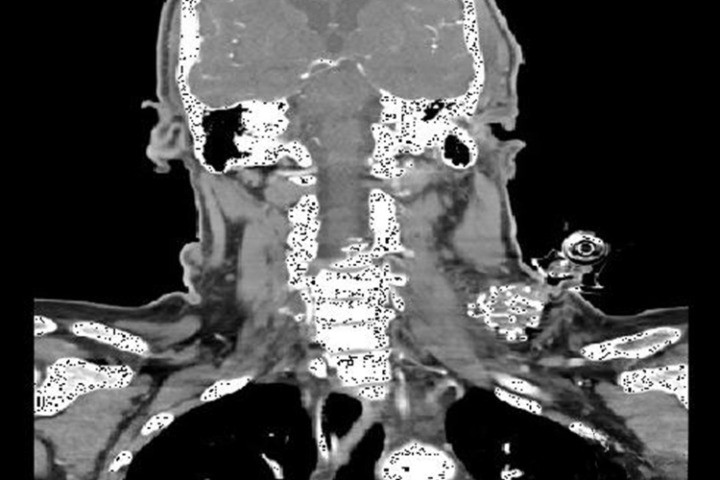

"Во второй половине 2016 года в Травмпункт Купер в Камдене, Нью-Джерси, США, поступила 44-летняя женщина с 25 проникающими ранениями в область груди и шеи. Когда пациентка поступила в больницу, она была без сознания, систолическое кровяное давление держалось на отметке 70. Пациентка была быстро осмотрена, было сделано переливание 4 единиц красных кровяных телец и 6 единиц свежей замороженной плазмы. Во время осмотра терапевты обнаружили два ранения в нижней части шеи в одном сантиметре над ключицей, кровотечение из этих ранений было неконтролируемым. Ранение было перевязано бинтом Combat Gauze, но бинт сразу же пропитался кровью. Пропитанный кровью бинт был удален и на оба ранения было помещено одно устройство iTClamp. Терапевты заметили, что кровь протекала и вокруг устройства. iTClamp было удалено, раны перевязали бинтом, а затем снова использовали iTClamp для изоляции раны. Врачи отметили, что сочетание бинта и iTClamp позволило им уменьшить площадь раны и закрыть кожу, что привело к хорошему гемостазу (рисунок 1). Все действия по остановке кровотечения заняли меньше двух минут, а сочетание материалов позволило врачам запечатать обе опасные раны. Состояние пациентки стабилизировалось, она была отправлена на компьютерную томографию для дальнейшего обследования. Возможность выполнить компьютерную томографию до оперативного вмешательства позволила хирургу оценить потенциальные зоны кровотечения и определить, откуда начинать хирургическое исследование 25 ран. Не было отмечено практически никакого рассеяния (за исключением небольшого рассеяние от шовных игл) и даже меньше, чем рассеяние от скоб (рисунки 2 и 3). После подтверждения отсутствия артериального кровотечения врачи сконцентрировались на ранах и переместили пациентку в операционную. Хирурги смогли провести подготовку к операции с зафиксированным устройством и сняли iTClamp перед началом хирургического исследования. Хирурги открыли близкие к ключице раны и исследовали их вглубь до ключицы, чтобы перевязать первую ветвь подключичной вены."

Рисунок 1